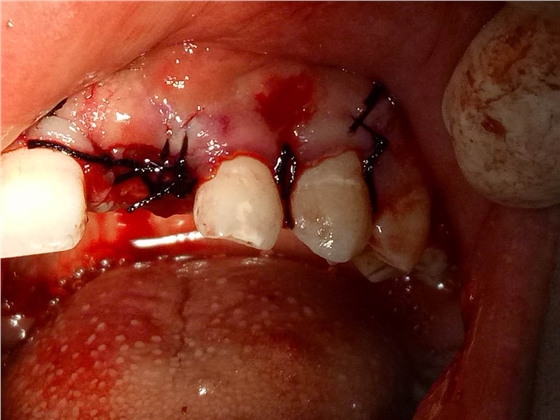

死髓牙2度,沒保留價值了,外傷造成的外吸收,即使到充也容易出問題。和患者溝通,要求做種植,用了兩個骨膠原,側切、尖牙沒事,側切做了一次根充